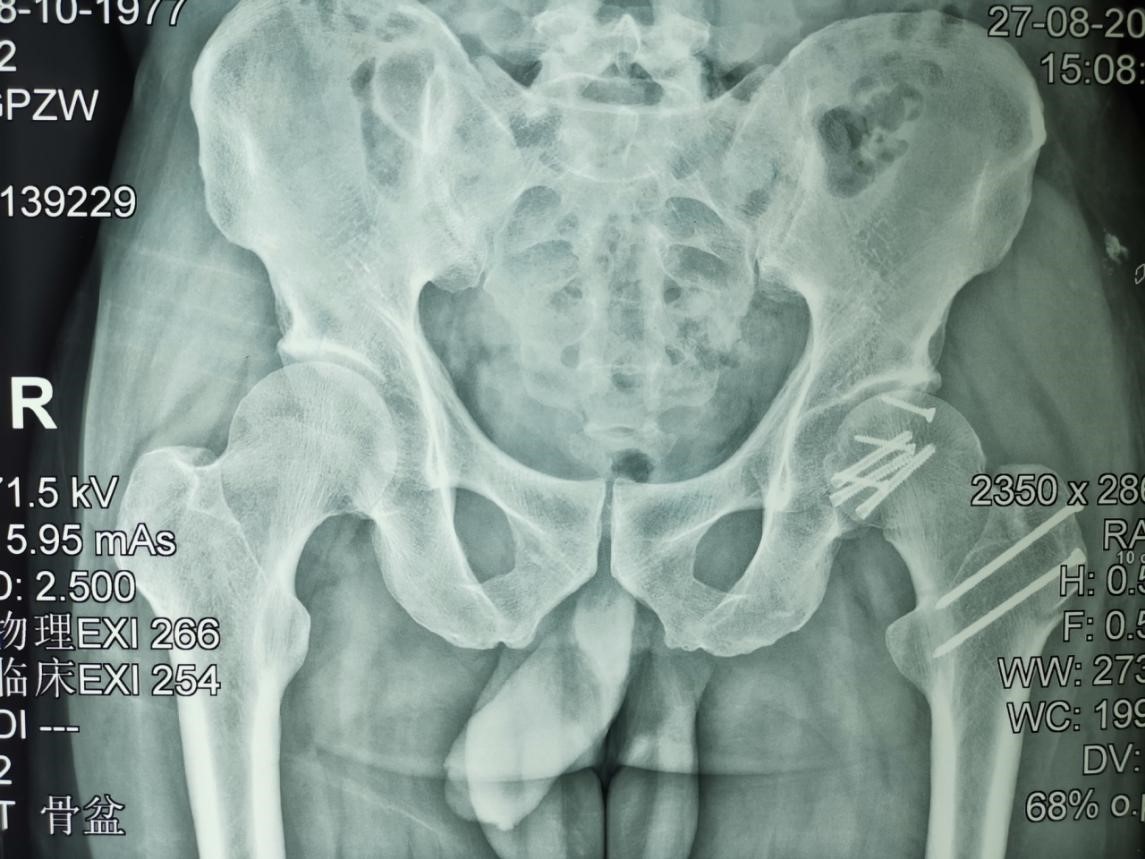

近日我科收治一名高能量车祸伤患者,该患男性,42岁,损伤机制为车祸方向盘损伤,患者系驾驶员,追尾前车,车体前方遭受巨大能量经左膝关节,通过股骨干传导至屈曲的左侧髋关节,造成股骨头骨折,髋关节后脱位,髋臼后壁骨折。查体:左下肢屈髋、内收、内旋位,左臀部后方肿胀淤青,可触及膨隆钝性骨性突起,左髋关节弹性固定位,屈伸、内收、外展、内外旋活动均受限。同侧坐骨神经及股动脉评估未见异常。左膝关节无肿胀,前后交叉韧带及内外侧韧带检查未见异常。

骨盆DR及三维CT

诊断为:1、股骨头骨折(左)2、髋关节脱位(左)3、髋臼后壁骨折(左)。